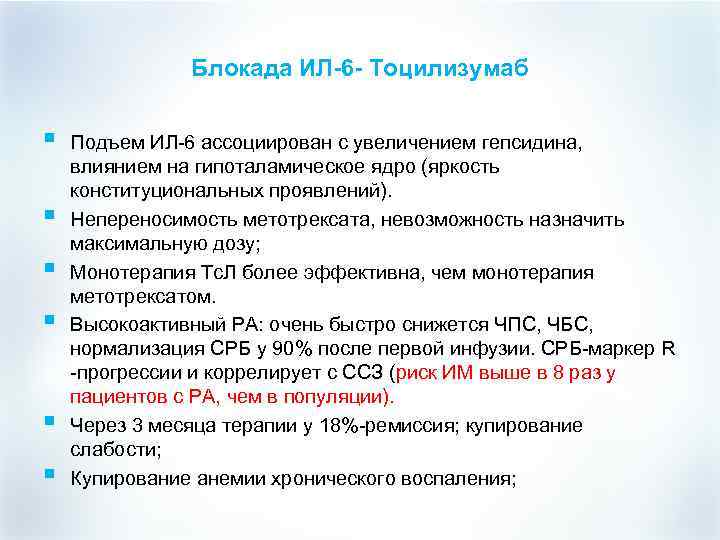

Блокада ИЛ-6 - Тоцилизумаб § § § Подъем ИЛ-6 ассоциирован с увеличением гепсидина, влиянием на гипоталамическое ядро (яркость конституциональных проявлений). Непереносимость метотрексата, невозможность назначить максимальную дозу; Монотерапия Тс. Л более эффективна, чем монотерапия метотрексатом. Высокоактивный РА: очень быстро снижется ЧПС, ЧБС, нормализация СРБ у 90% после первой инфузии. СРБ-маркер R -прогрессии и коррелирует с ССЗ (риск ИМ выше в 8 раз у пациентов с РА, чем в популяции). Через 3 месяца терапии у 18%-ремиссия; купирование слабости; Купирование анемии хронического воспаления;

Блокада ИЛ-6 - Тоцилизумаб § § § Подъем ИЛ-6 ассоциирован с увеличением гепсидина, влиянием на гипоталамическое ядро (яркость конституциональных проявлений). Непереносимость метотрексата, невозможность назначить максимальную дозу; Монотерапия Тс. Л более эффективна, чем монотерапия метотрексатом. Высокоактивный РА: очень быстро снижется ЧПС, ЧБС, нормализация СРБ у 90% после первой инфузии. СРБ-маркер R -прогрессии и коррелирует с ССЗ (риск ИМ выше в 8 раз у пациентов с РА, чем в популяции). Через 3 месяца терапии у 18%-ремиссия; купирование слабости; Купирование анемии хронического воспаления;